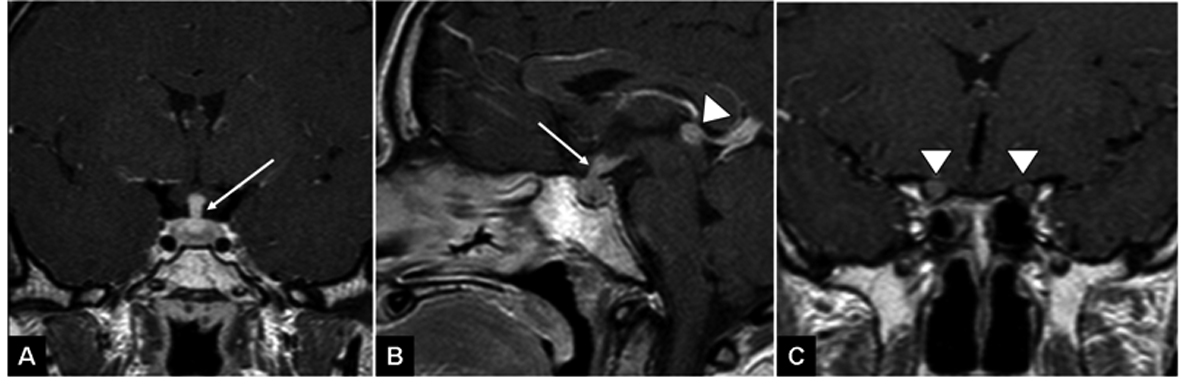

The patient was a 28-year-old male from Jewish-Ethiopian descent, with no history of chronic diseases. He presented with right eye pain lasting for three weeks and loss of vision in the same eye. Fundoscopy showed bilateral papilledema and unknown cells within the vitreous. A brain MRI showed enhancement of the pituitary infundibulum and thickening of the optic nerves and optic chiasm, as well as an enhancing lesion in the pineal gland (Fig. 1). Whole body CT scan showed a left sided chest wall lesion with destruction of the 6th rib (Fig. 2). Tumor markers, including beta-HCG, alpha-FP, were within the normal limits. Since the differential diagnosis of the CNS lesions included sarcoid, angiotensin and calcium levels in the blood and CSF were examined and found to be within the normal limits. Repeated CSF examination showed normal biochemistry, and cytotyping of lymphocytes from the lumbar puncture was compatible with reactive lymphocytes; malignant cells were not demonstrated. CSF was negative for CMV DNA, Ig for West Nile virus, HHV-6 DNA, HSV-1 DNA, Varicella Zoster DNA. A core needle biopsy was taken from the pleural lesion and was consistent with poorly differentiated PNET with negative FISH and PCR for translucation (t 11; 22). The tumor cells stained positively via immunohistochemistry for synaptophysin and CD-56, but were negative for LCA, CD-20, CD-3, CD-43, TdT, PAX-5; vimentin, FLI-1; cytokeratin, Cytokeratin-7, Cytokeratin -20, P-63, and inconclusive for chromogranin. Bone marrow aspiration was normal without evidence of malignant cells. The possibility of taking a biopsy or cytology from the brain lesion or the vitreous was ruled out by the neurosurgeons and ophthalmologists in our institution, due to the high surgical risk.

![]() Click for large image | Figure 1. T1 weighted images following gadolinium injection demonstrate thickened pituitary infundibulum (arrow A, B), thickened and enhancing optic nerves (arrowheads C) and a nodular enhancing pineal lesion (arrowhead B). |

On presentation, the patient was started on high doses of steroids with immediate improvement of his eyesight. After histological evidence of PNET, chemotherapy was started with etoposide-ifosfamide alternating with vincristine, doxorubicin and cyclophosphamide cycles. A brain MRI on the 4th day of the first chemotherapy cycle (and after two weeks of steroid treatment) revealed disappearance of the lesion in the pineal gland and partial resolution of the other CNS sites. The chest wall lesion regressed significantly after chemotherapy.